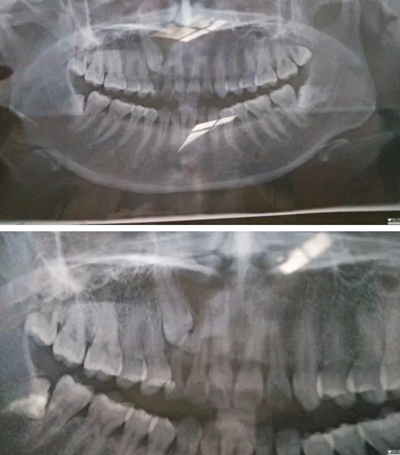

2017年6月18日,牙疼…之前補過一次,這次估計是發(fā)炎了,然后被伊森告知乳牙滯留,恒牙阻生,要拍片確認恒牙是否完好,才能進行下一步…鎮(zhèn)醫(yī)院,設備不齊全,伊森建議去大醫(yī)院拍片…

心里著急,第二天就跑到廣東省口腔醫(yī)院花了一天的時間排隊拍片,然后被伊森建議去矯正科詳細咨詢…然后矯正伊森就跟我說了大概治療方案,時間和費用,先拔掉四顆智慧牙,然后帶牙套矯正牙齒,期間會拔掉小虎牙給埋伏牙做牽引(我情況比較復雜,下面有兩顆埋伏牙,還得拔掉其中一顆)╭(°A°`)╮而且還不一定牽引成功,如果不成功,最后矯正后期還要種植牙齒(?_?)…要花3-4W,長達2年時間…當時就震驚了,從沒想過自己這口牙辣么貴,辣么麻煩…

跟LG一起確定了矯正之后,立馬打電話給伊森預約了7.3號,然后LG陪我一起去了醫(yī)院,伊森詳細了解了婚姻狀況,生娃狀況(對于我已經(jīng)有兩個娃的事實表示了各種驚訝),然后拍片,倒模具,定制方案,約定下次就診時間…